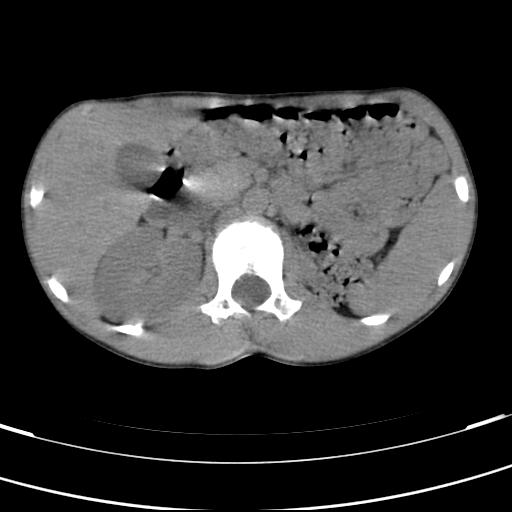

标题: PED3157:左肾缺如,请教脾脏的改变?、、

男孩,9岁。胃部不适。

脾脏变异,左肾未见,游走、异位、发育不全都要可能,增强或ivp造影。

脾脏位于左侧,但数个脾脏呈分离状态,左肾缺如,右肾代偿肥大。考虑多脾综合征。